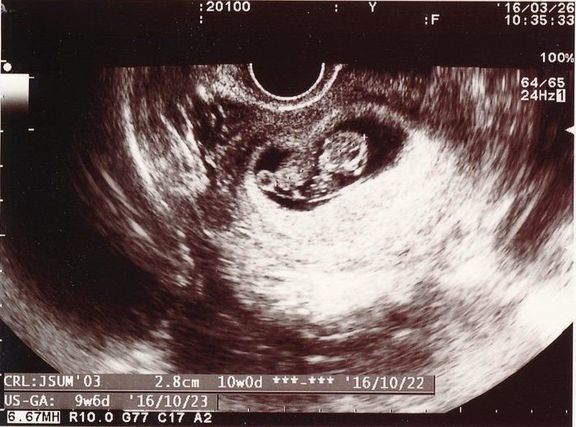

"おなかの中はどうなっていくの? エコー写真で振り返る、高齢ママのはじめての妊娠生活" -

思いがけず授かった2人目は43歳の高齢出産!健診は不安と期待との板挟み! -